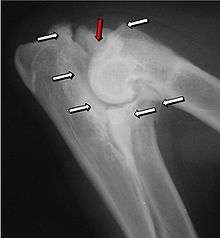

Most primary lesions are related to osteochondrosis, which is a disease of the joint cartilage and specifically Osteochondritis dissecans (OCD or OD), the separation of a flap of cartilage on the joint surface. Other common causes of elbow dysplasia included ununited anconeal process (UAP) and fragmented or ununited medial coronoid process (FCP or FMCP).[1]

The most common cause is osteochondrosis, which is a disease of the joint cartilage, and specifically Osteochondritis dissecans (OCD or OD), the separation of a flap of cartilage from the joint surface[1] as a result of avascular necrosis, which in turn arises from failed blood flow in the subchondral bone.[3] Other common causes of elbow dysplasia included ununited anconeal process (UAP) and fractured or ununited medial coronoid process (FCP or FMCP).[1]

In OCD, the normal change of cartilage to bone in the development of the joint fails or is delayed. The cartilage continues to grow and may split or become necrotic. The cause is uncertain, but possibly includes genetics, trauma, and nutrition (including excessive calcium and decreased Vitamin C intake).[4] OCD lesions are found in the elbow at the medial epicondyle of the humerus. Specific conditions related to OCD include fragmentation of the medial coronoid process of the ulna (FMCP) and an ununited anconeal process of the ulna (UAP). All types of OCD of the elbow are most typically found in large breed dogs, with symptoms starting between the ages of 4 to 8 months.[4] Males are affected twice as often as females. The disease often affects both elbows (30 to 70 percent of the time), and symptoms include intermittent lameness, joint swelling, and external rotation and abduction of the paw.[5] Osteoarthritis will develop later in most cases.

UAP is caused by a separation from the ulna of the ossification center of the anconeal process.[6] FMCP is caused by a failure of the coronoid process to unite with the ulna. OCD of the medial epicondyle of the humerus is caused by disturbed endochondral fusion of the epiphysis of the medial epicondyle with the distal end of the humerus, which may in turn be caused by avulsion of the epiphysis.[7]